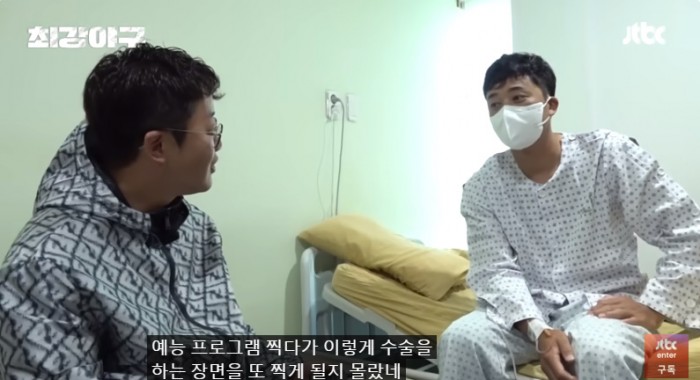

[최강야구] 수술받고도 방출 안 당한 이택근이 진짜 영리하고 대단했던 이유...jpg